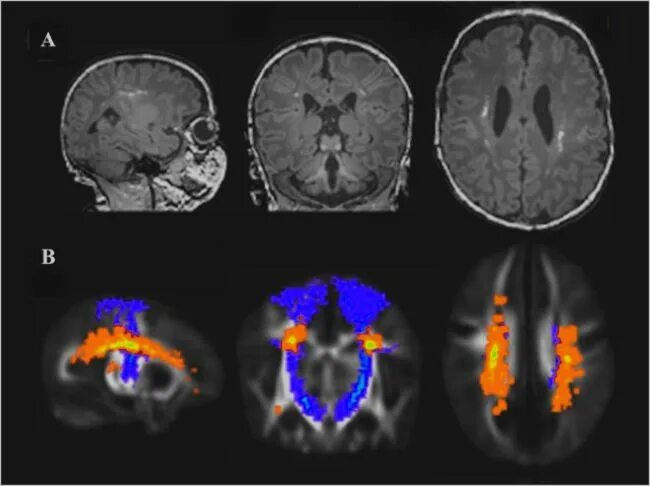

Очаг глиоза в теменной доле